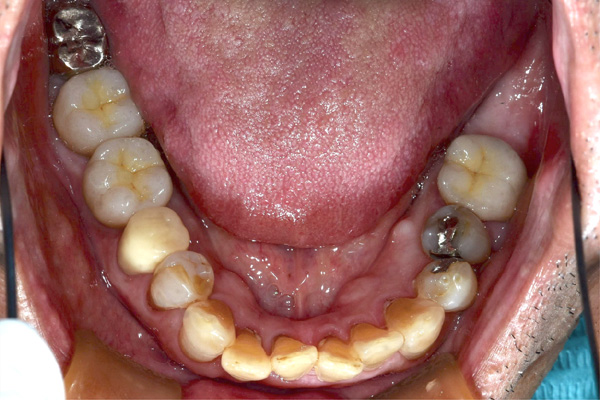

| 年代・性別 | 30代 女性 |

|---|---|

| 主訴 | 左上の乳歯がグラグラしてきた |

| 治療期間 | 約12ヶ月 |

| 費用 | 550,000円 |

| 治療内容 | インプラント、骨造成、セラミック修復 |

| 治療に伴うリスク | インプラント周囲炎 セラミックの破折、脱離 |